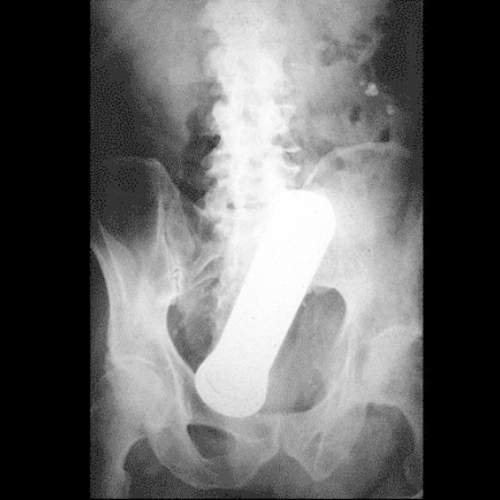

這張異物突入X光照當中的物體是顆砲彈,故事是來自英國倫敦的一位二戰老兵~他長期受到痔瘡折磨所苦,因此有時他會用砲彈將痔瘡塞進屁屁裡~結果有一天用力過度砲彈被卡在裡面,後來送醫時院方考慮到這是真正的砲彈,因此還請來了拆彈小組到現場